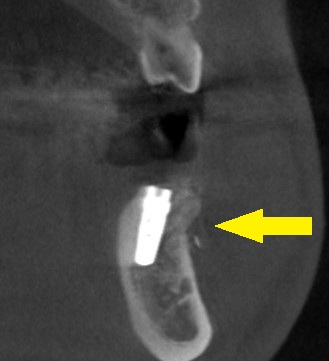

本日、同部に、インプラント埋入術、骨造成術を行っております。

下の写真下段右が手術後のCTです。

インプラントの外側に、補填した人工骨が白く写っています。